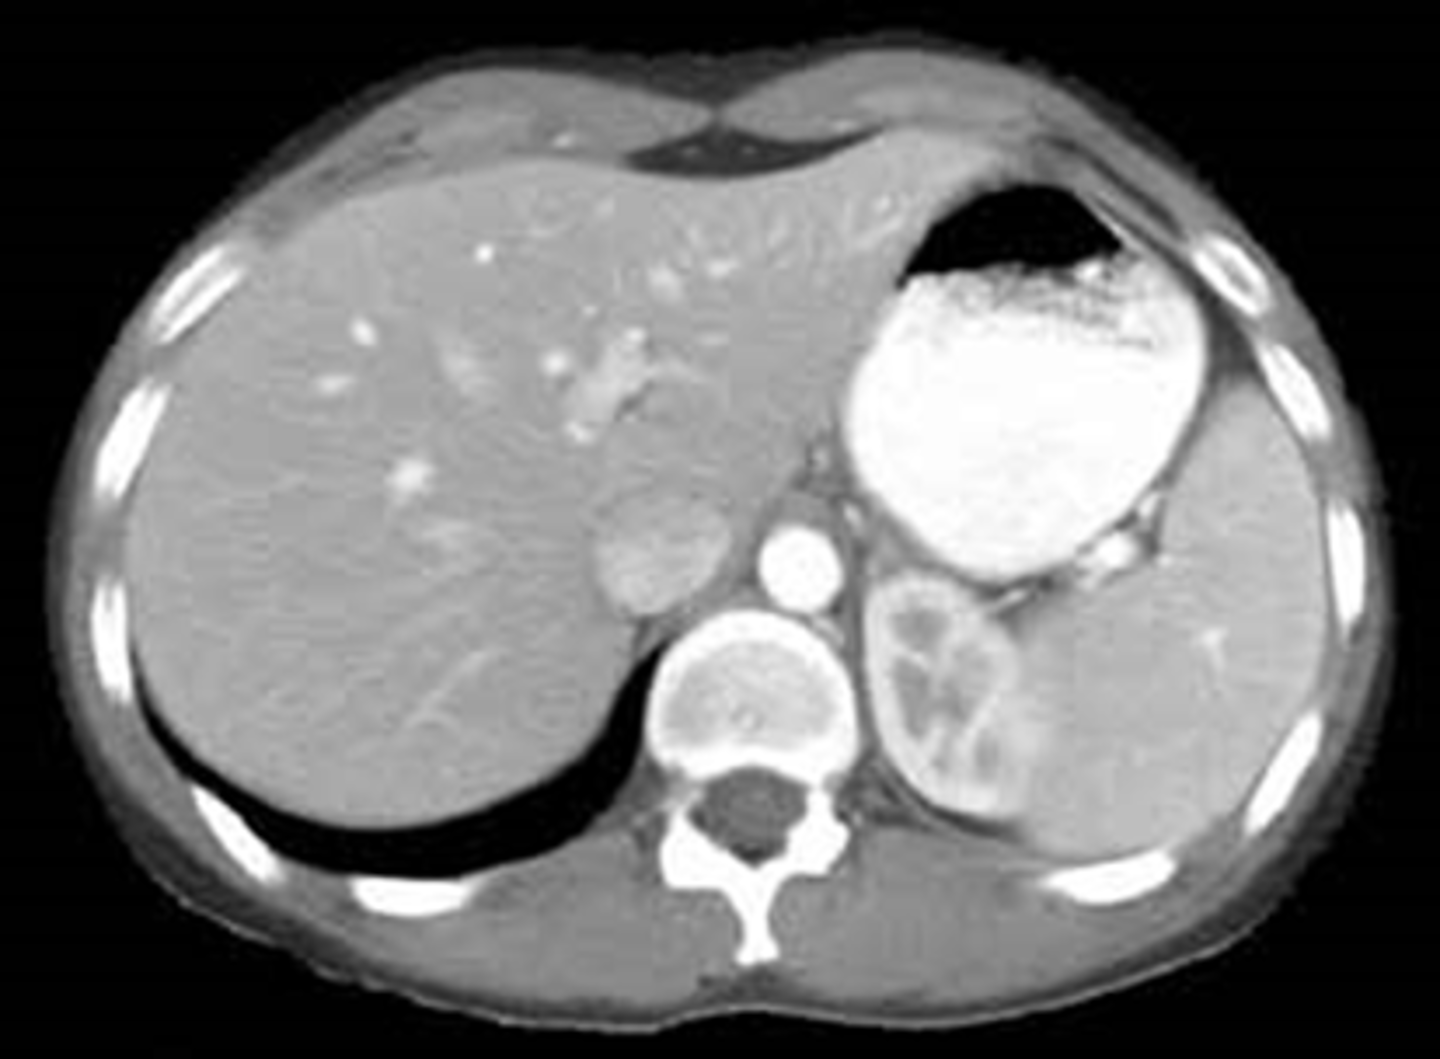

A:

WHITE ARROWS: soft tissue mass on LUQ

BLACK ARROW: displacement of bowels to the right

B: CT of the same patient

WHITE ARROW: large renal cyst arising from left kidney, displacing it and surrounding bowel.

BLACK ARROW: left kidney.

S: spleen, compressed by cyst.